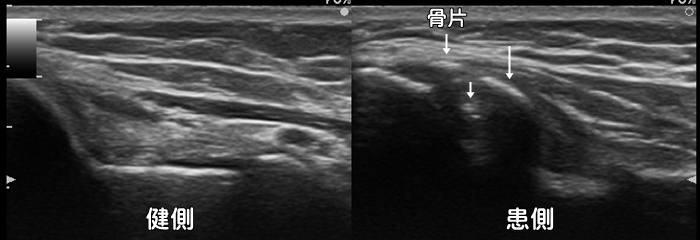

野球肘・離断性骨軟骨炎

野球をしていて肘の内側や外側に痛みを感じた場合、内側型・外側型の野球肘を疑います。自覚症状は圧痛・外反ストレス痛・可動域制限です。ただし外側型の野球肘は初期では自覚症状に乏しく、症状が現れた頃にはかなり進行して手術を必要とすることもある為、エコーによる早期発見が重要です。